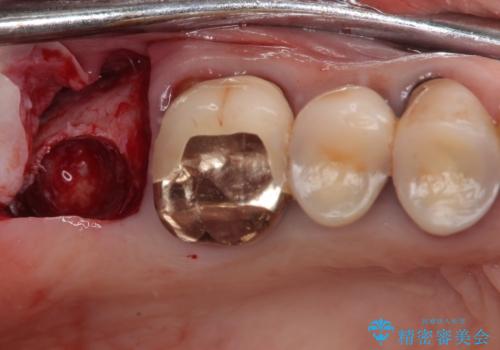

- 食事が取れないほどの激痛で、インプラント治療を希望して来院された患者様です。

近医にてクラウンを除去してもらった状態での来院でした。

遠心が歯根破折しており、歯槽骨が著しく吸収している状態であったため、抜歯即時でのインプラント埋入は断念し、2ヶ月ほど待機してから埋入することとしました。